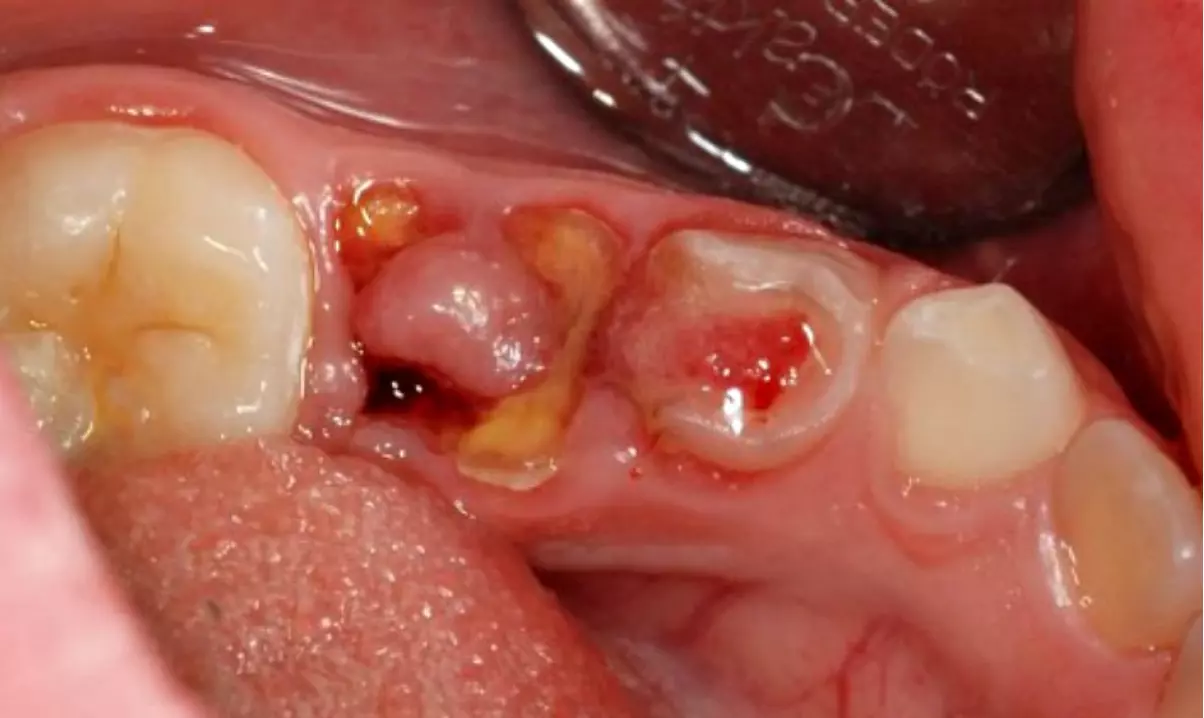

Гипертрофический пульпит

Гипертрофический пульпит возникает, если пульпа продолжительное время контактирует с полостью рта. Отвечая на механические раздражители, она разрастается в виде красного “гриба”, прорастающего из зуба. Обычно такой пульпит не беспокоит ребенка. Иногда детям не нравится, что вырост травмируется и кровоточит во время еды.

Все виды необратимых пульпитов сопровождаются наличием кариозной полости. В случае с молочными зубами она может быть небольшой. В постоянных зубах пульпит может развиваться, как осложнение глубокого кариеса. Старые большие пломбы у подростков – еще одно место, где можно заподозрить хронический пульпит.